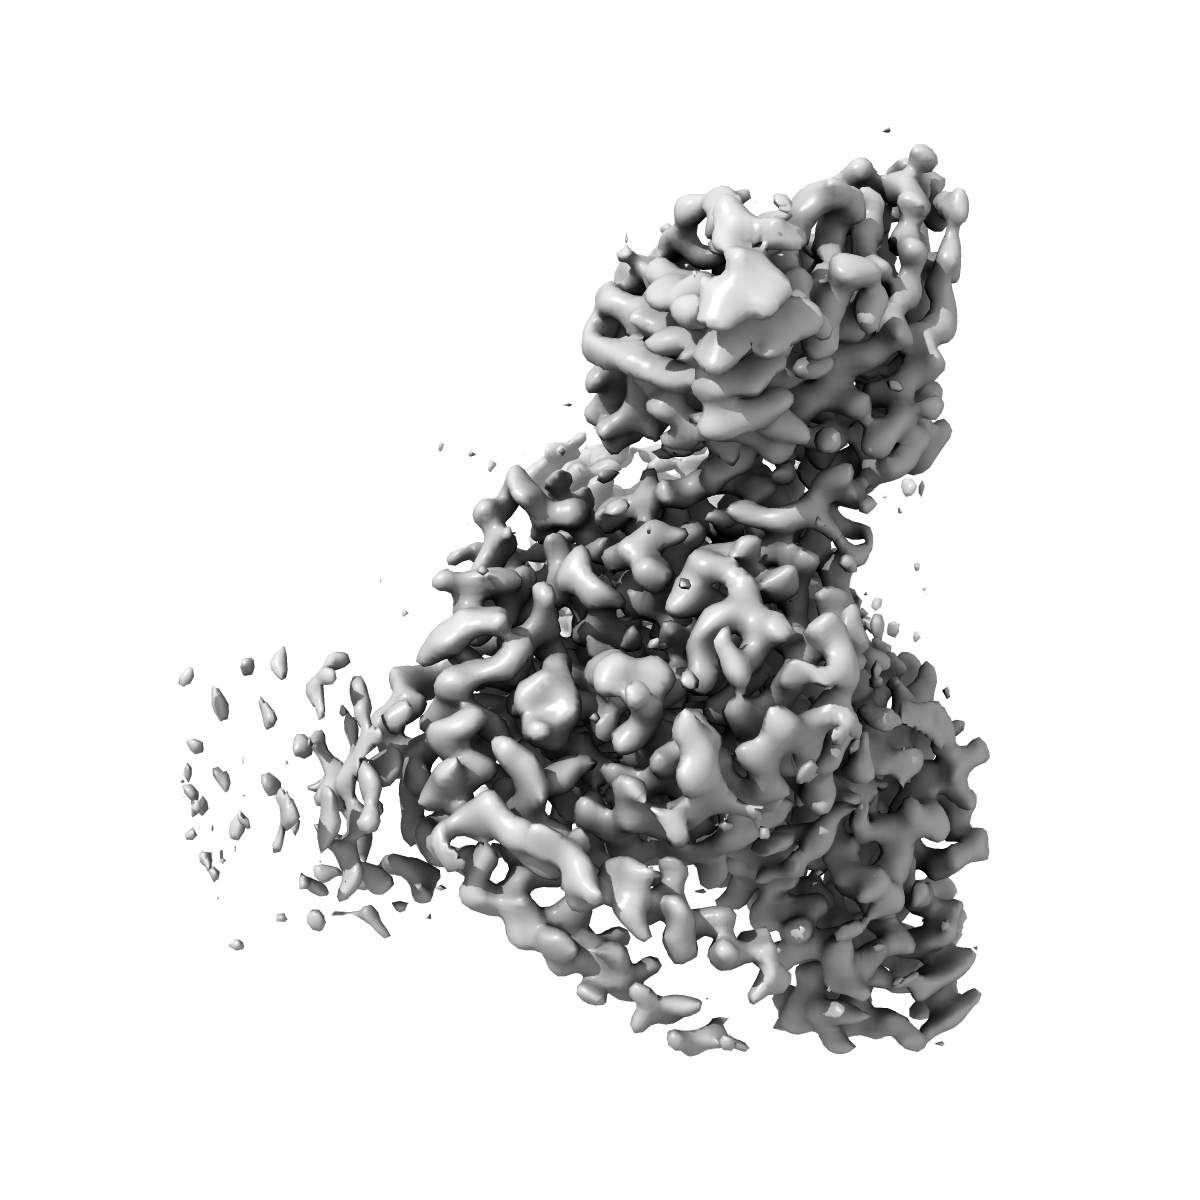

Cryo-EM structure of the DHA bound FFA1-Gq complex

Sample: DHA-FFA1-miniGq complex

Structural basis for the ligand recognition and signaling of free fatty acid receptors.

Zhang X , Guseinov AA , Jenkins L, Li K , Tikhonova IG , Milligan G , Zhang C

(2024) Sci Adv , 10 , eadj2384 - eadj2384